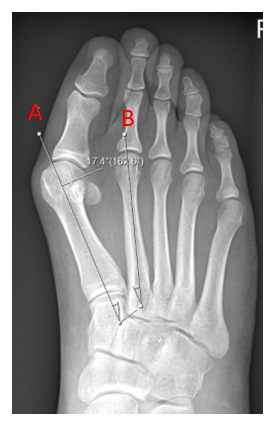

Metatarsus adductus is the medial deviation of the metatarsals and often present with a bunion. In some cases, patients also develop arthritis in the midfoot with additional pain. The cause of metatarsus adductus is not fully understood with a combination of nature and nurture suspected. It can occur in isolation or as part of a more complex condition such as club foot.

Metatarsus adductus surgery normally involves realignment by fusing the medial midfoot joints. In a paper published by the department the outcomes following surgery on 59 patients were examined.

This X-ray shows a significant bunion (hallux valgus) only. The first metatarsal (a) in isolation has drifted away from the second (b)

This X-ray shows a bunion, however the metatarsus adductus angle is significant, reflecting the medial drift of the first three metatarsals towards the inside of the foot. Now the bunion cannot be corrected by just addressing the first metatarsal alone.

The far X-ray shows the bunion and metatarsus adductus angles having been successfully addressed by fusion the medial three metatarsals with screw fixation.